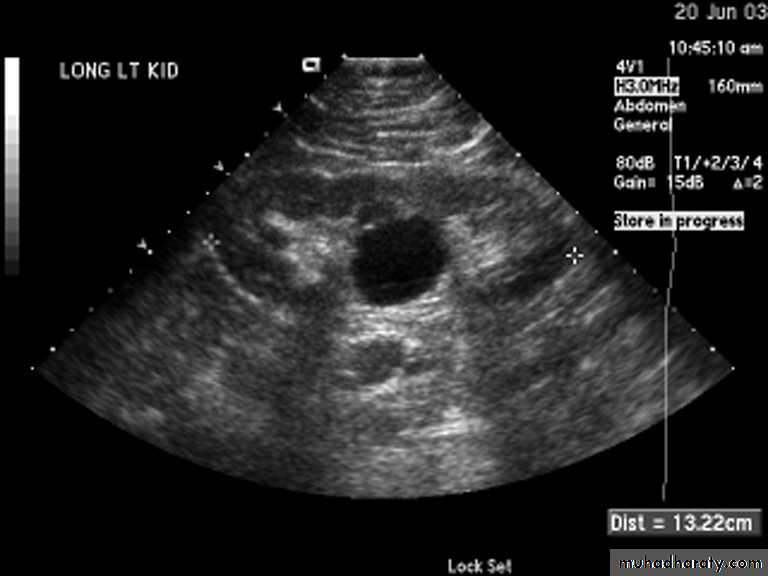

Simple (solitary) renal cyst

Common condition.

single or multiple.

uni or bilateral.

Congenital or acquired.

Usually asymptomatic.

In 10% symptomatic: pain, heaviness, infection, bleeding inside the cyst or

pressure effect on the ureter causing hydronephrosis.

Diagnosis

Examination: usually –ve, big cyst cause painless loin mass, & painful if complicated by bleeding or infectionU/S: echo free area (cystic lesion)